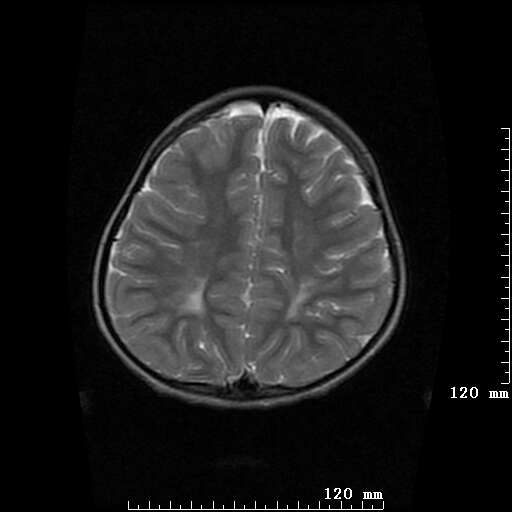

女,7岁,三岁才说话、走路。现智力尚可,走路不稳。临床怀疑大脑发育不全。

脑折质变薄,双侧侧脑室稍扩张,支持考虑脑折质发育不良

侧脑室周围白质软化症。

侧脑室周围白质数量减少,侧脑室不对称性扩大,左侧侧脑室后角呈方形改变,脑沟加深,结合临床考虑脑室周围白质软化症(pvl)。期待结果!

支持脑白质发育不良。